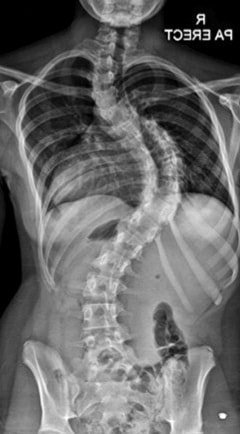

Създателите на сериала казали, че работят много усилено за да запазят "гръбнака" на историята

Ето го и гръбнака